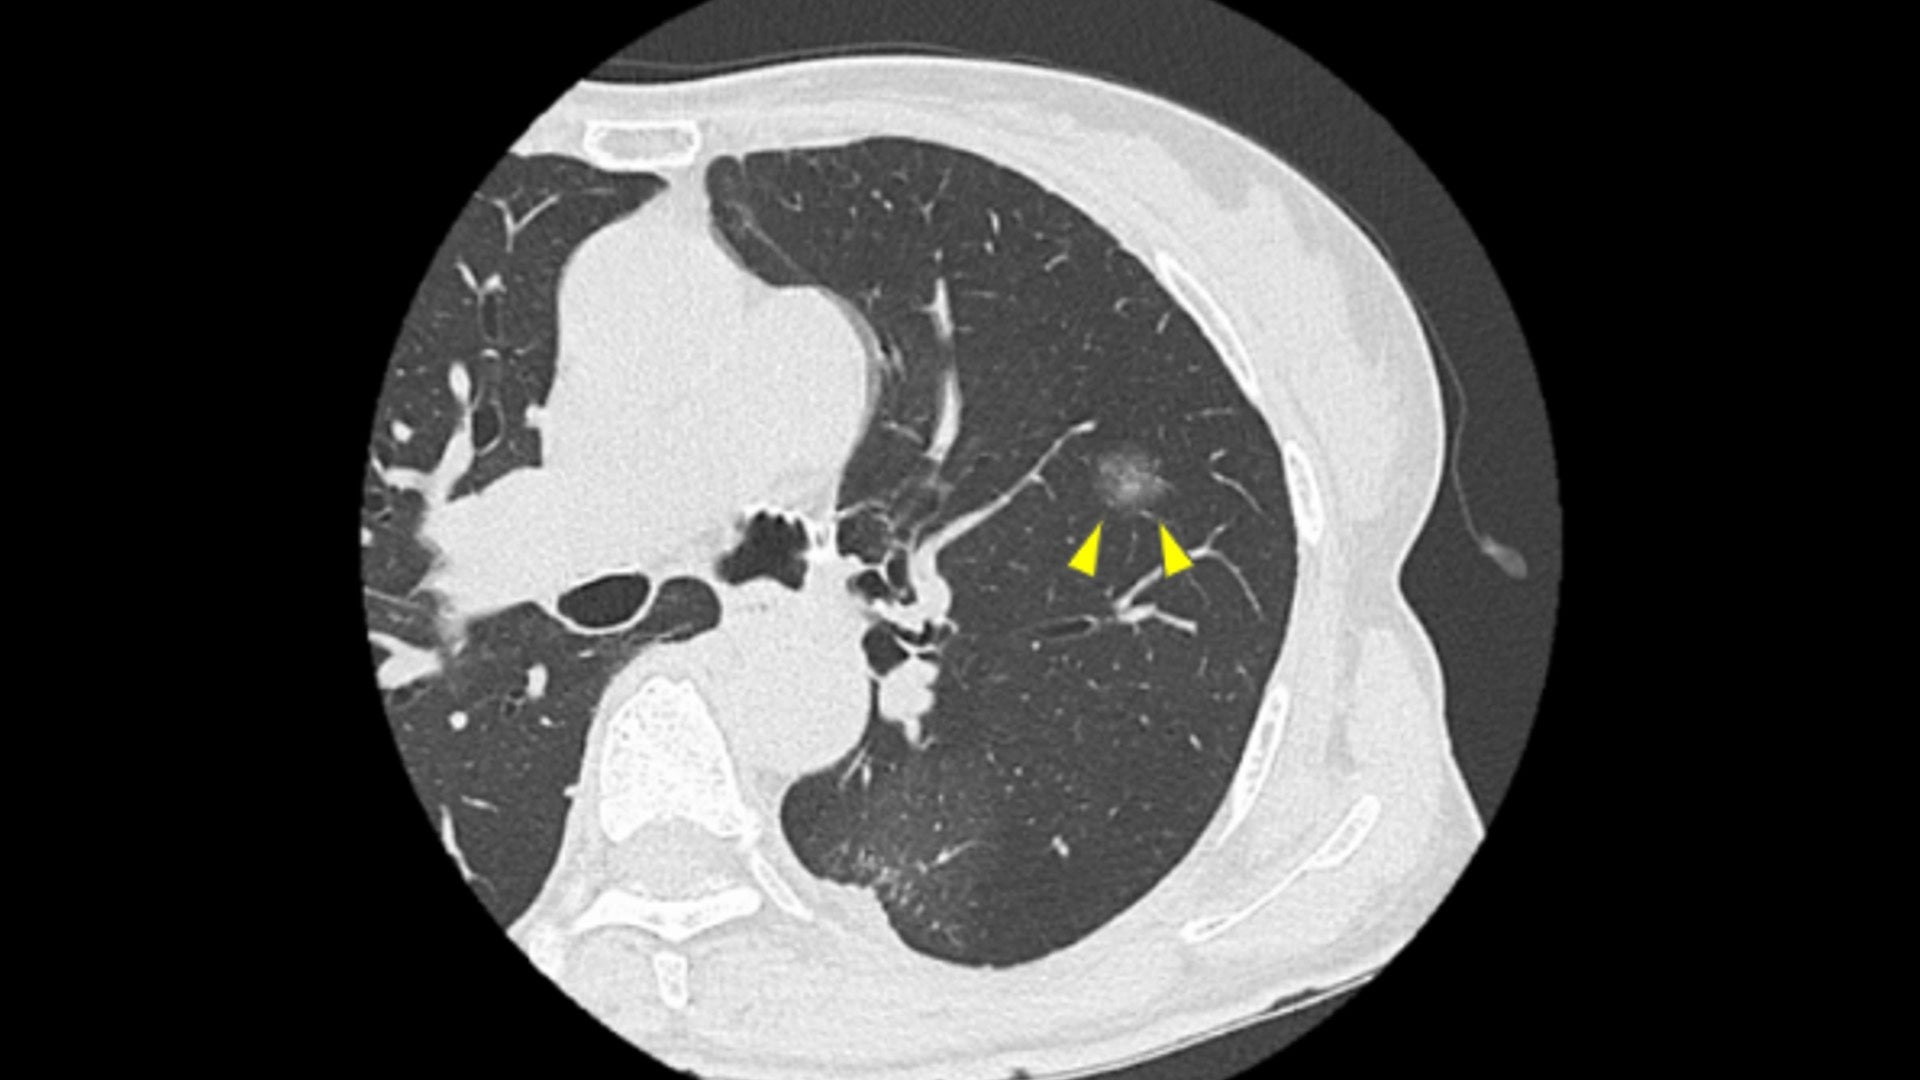

肺に影が見つかった時に最も重要なのは「手術が必要な肺がんらしい影なのか、手術せずに経過観察で良いタイプの影なのか」をできる限り早く正確に見極めることです。そして、CT画像から手術の必要性を最終的に判断できるのは「肺がん手術を専門とする呼吸器外科医」ですが、そういう医師にたどり着くまでに長い時間がかかっている患者さまが多いです。

当院では、肺がん治療を専門とする呼吸器外科医、麻酔科医を含む4名の専門医が迅速にCT画像を確認し、患者さまがすぐに相談できる診療体制を整えていますので、初診の段階から手術すべきかどうかのご提案が可能です。もちろん、その上で経過観察が適切であると判断する場合もありますが、どれだけ小さくても肺に影がある場合、一度は呼吸器外科医に診てもらっておくことで、手術の機会を逸する可能性は低くなり、患者さまが抱える不安を軽減できると考えます。